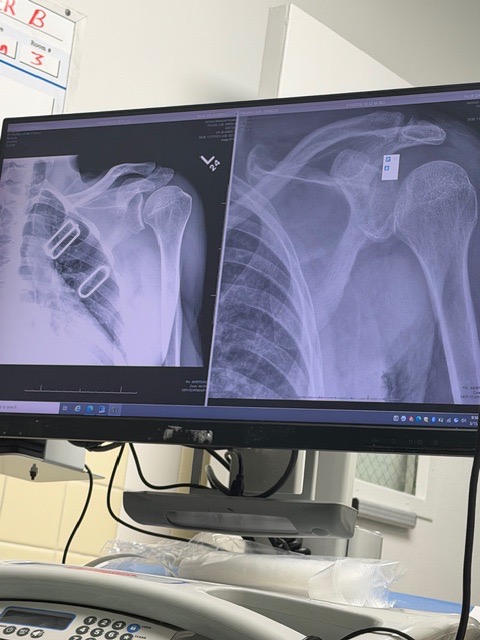

On March 14th, local friend and avid cyclist Luis Pagan was finishing his usual Saturday endurance training ride in Key Biscayne. After coming down the Rickenbacker Bridge, he accidentally hit something on the bike lane and unfortunately lost control of the handlebar, causing him to fall off the bike at high speed. Other cyclists in the area noticed he was hurt and offered immediate assistance. Paramedics arrived shortly after and transferred him to the ER at Jackson Memorial Hospital. Luis was seen by multiple doctors and specialists, including an orthopedic surgeon and trauma team, who confirmed he has a fractured hip, dislocated shoulder, sprained wrist, and multiple skin burn lacerations.

Luckily, Luis did not suffer any head injuries. However, CT scans show that he will need further examination (MRI) and treatment for his injured shoulder and fractured hip. After being discharged from the hospital, he has been instructed not to put any weight on his right leg for at least six weeks and then it will require several weeks of physical therapy . Please support Luis' recovery journey with any donations so that he can get a speedy recovery and back on his feet. The funds raised will go toward medical bills, living expenses, and therapeutic items to support his recovery.